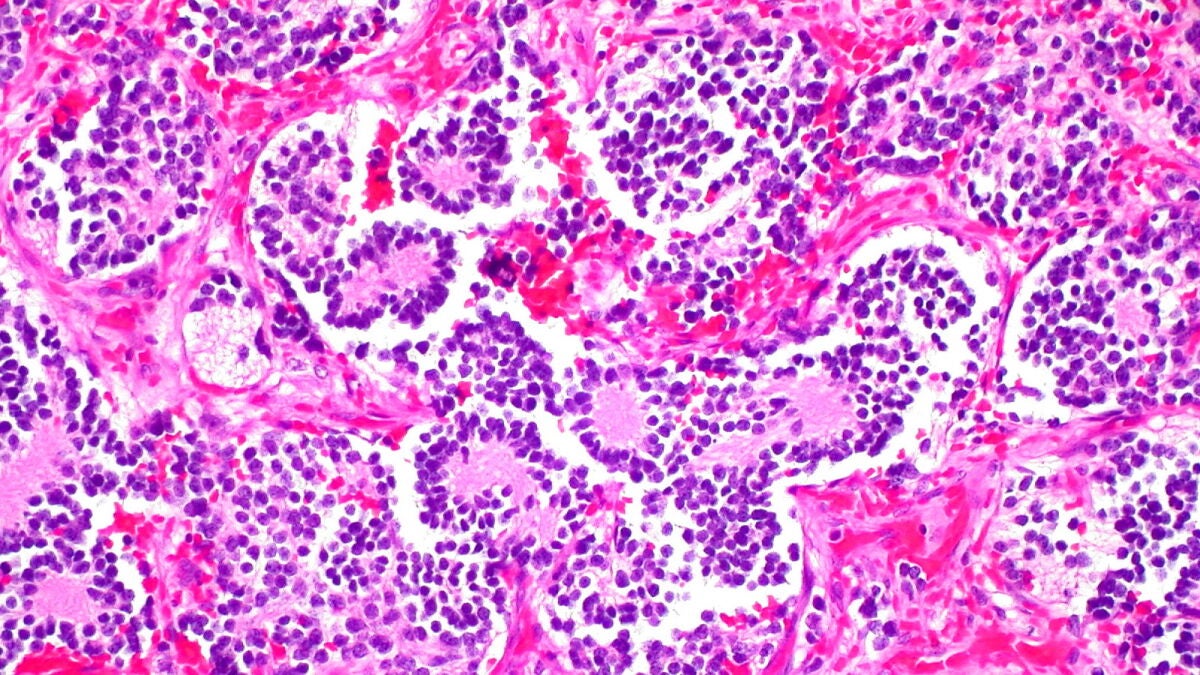

Ahora, un equipo de científicos del Instituto Karolinska y la Universidad de Lund (Suecia) han identificado una nueva estrategia de tratamiento para este tipo de tumores. De acuerdo con el estudio, publicado en Proceedings of the National Academy of Sciences, mediante la combinación de dos inhibidores de enzimas antioxidantes, han convertido células cancerosas de ratones en células nerviosas sanas.

El equipo de Arsenian Henriksson ha demostrado que la inhibición de dos enzimas específicas, PRDX6 y GSTP1, podría ser una alternativa al tratamiento con ácido retinoico.

"Al inhibir estas enzimas en cultivos celulares, así como en modelos murinos, algunas células tumorales mueren mientras que otras maduran y se convierten en neuronas sanas y activas, lo que dificulta el crecimiento tumoral", añade Judit Liaño-Pons, experta española en biología oncológica molecular y coautora del estudio.